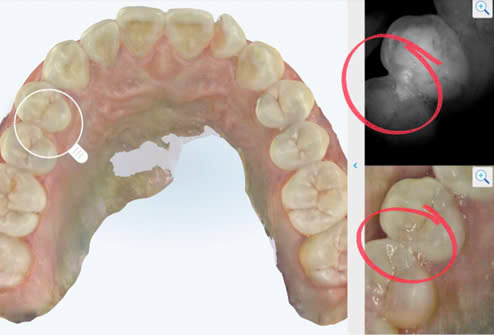

5. Case lâm sàng

Tính năng NIRI tích hợp trong máy quét cho phép phát hiện những vùng nghi ngờ có tổn thương sâu răng mặt bên.

Kiểm tra lại bằng cách chụp phim cánh cắn – “tiêu chuẩn vàng” trong chẩn đoán sâu răng mặt bên: Có tổn thương mất khoáng vùng R14-15

Thực tế trên lâm sàng:

Sau khi làm sạch lỗ sâu: